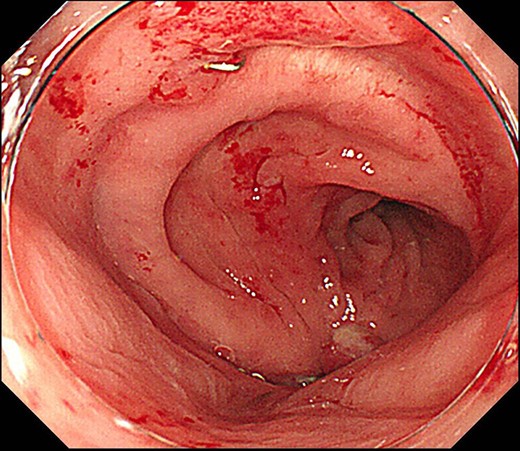

Case 1 was a 71-year-old man with a BMI of 29.7 kg/m2. Laparoscopic low anterior resection (LAR) and ileostomy was performed for rectal cancer in 2017 years. Postoperative fever and lower abdominal pain were noted, and colonoscopy was performed, and anastomotic leakage was noted with a correction of about 1/2 around the 6 o’clock direction of the anastomotic region, and fistula and formation of a large abscess cavity. After identification (Fig. 1), a tube was inserted for drainage and conservative treatment was performed. The patient was discharged on POD 46. Four months after the operation, marked improvement in the abscess cavity was noted but still remained (Fig. 2a and b). Anastomotic leakage was almost improved by colonoscopy at 17 months after surgery, but at the preference of the patient we performed colostomy 22 months after surgery (Fig. 3). It took a long time to improve intestinal movement of the colon because the large intestinal tract had not been used for a long time, and conservative treatment was performed using a nasogastric tube for paralytic ileus. Diet was initiated 7 days after surgery, and the patient was discharged from the hospital 14 days after surgery. The Wexner score [2] was 19 points one month after closure, 17 points 3 months after the operation and 16 points after 6 months after the operation, and severe anal dysfunction was observed, but gradually improved.

Colonoscopy revealed a true lumen (circle), an anastomotic site (triangle) and a cavity due to suture failure (arrow).